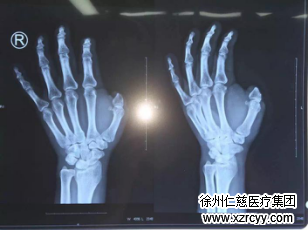

x线片显示拇指缺失